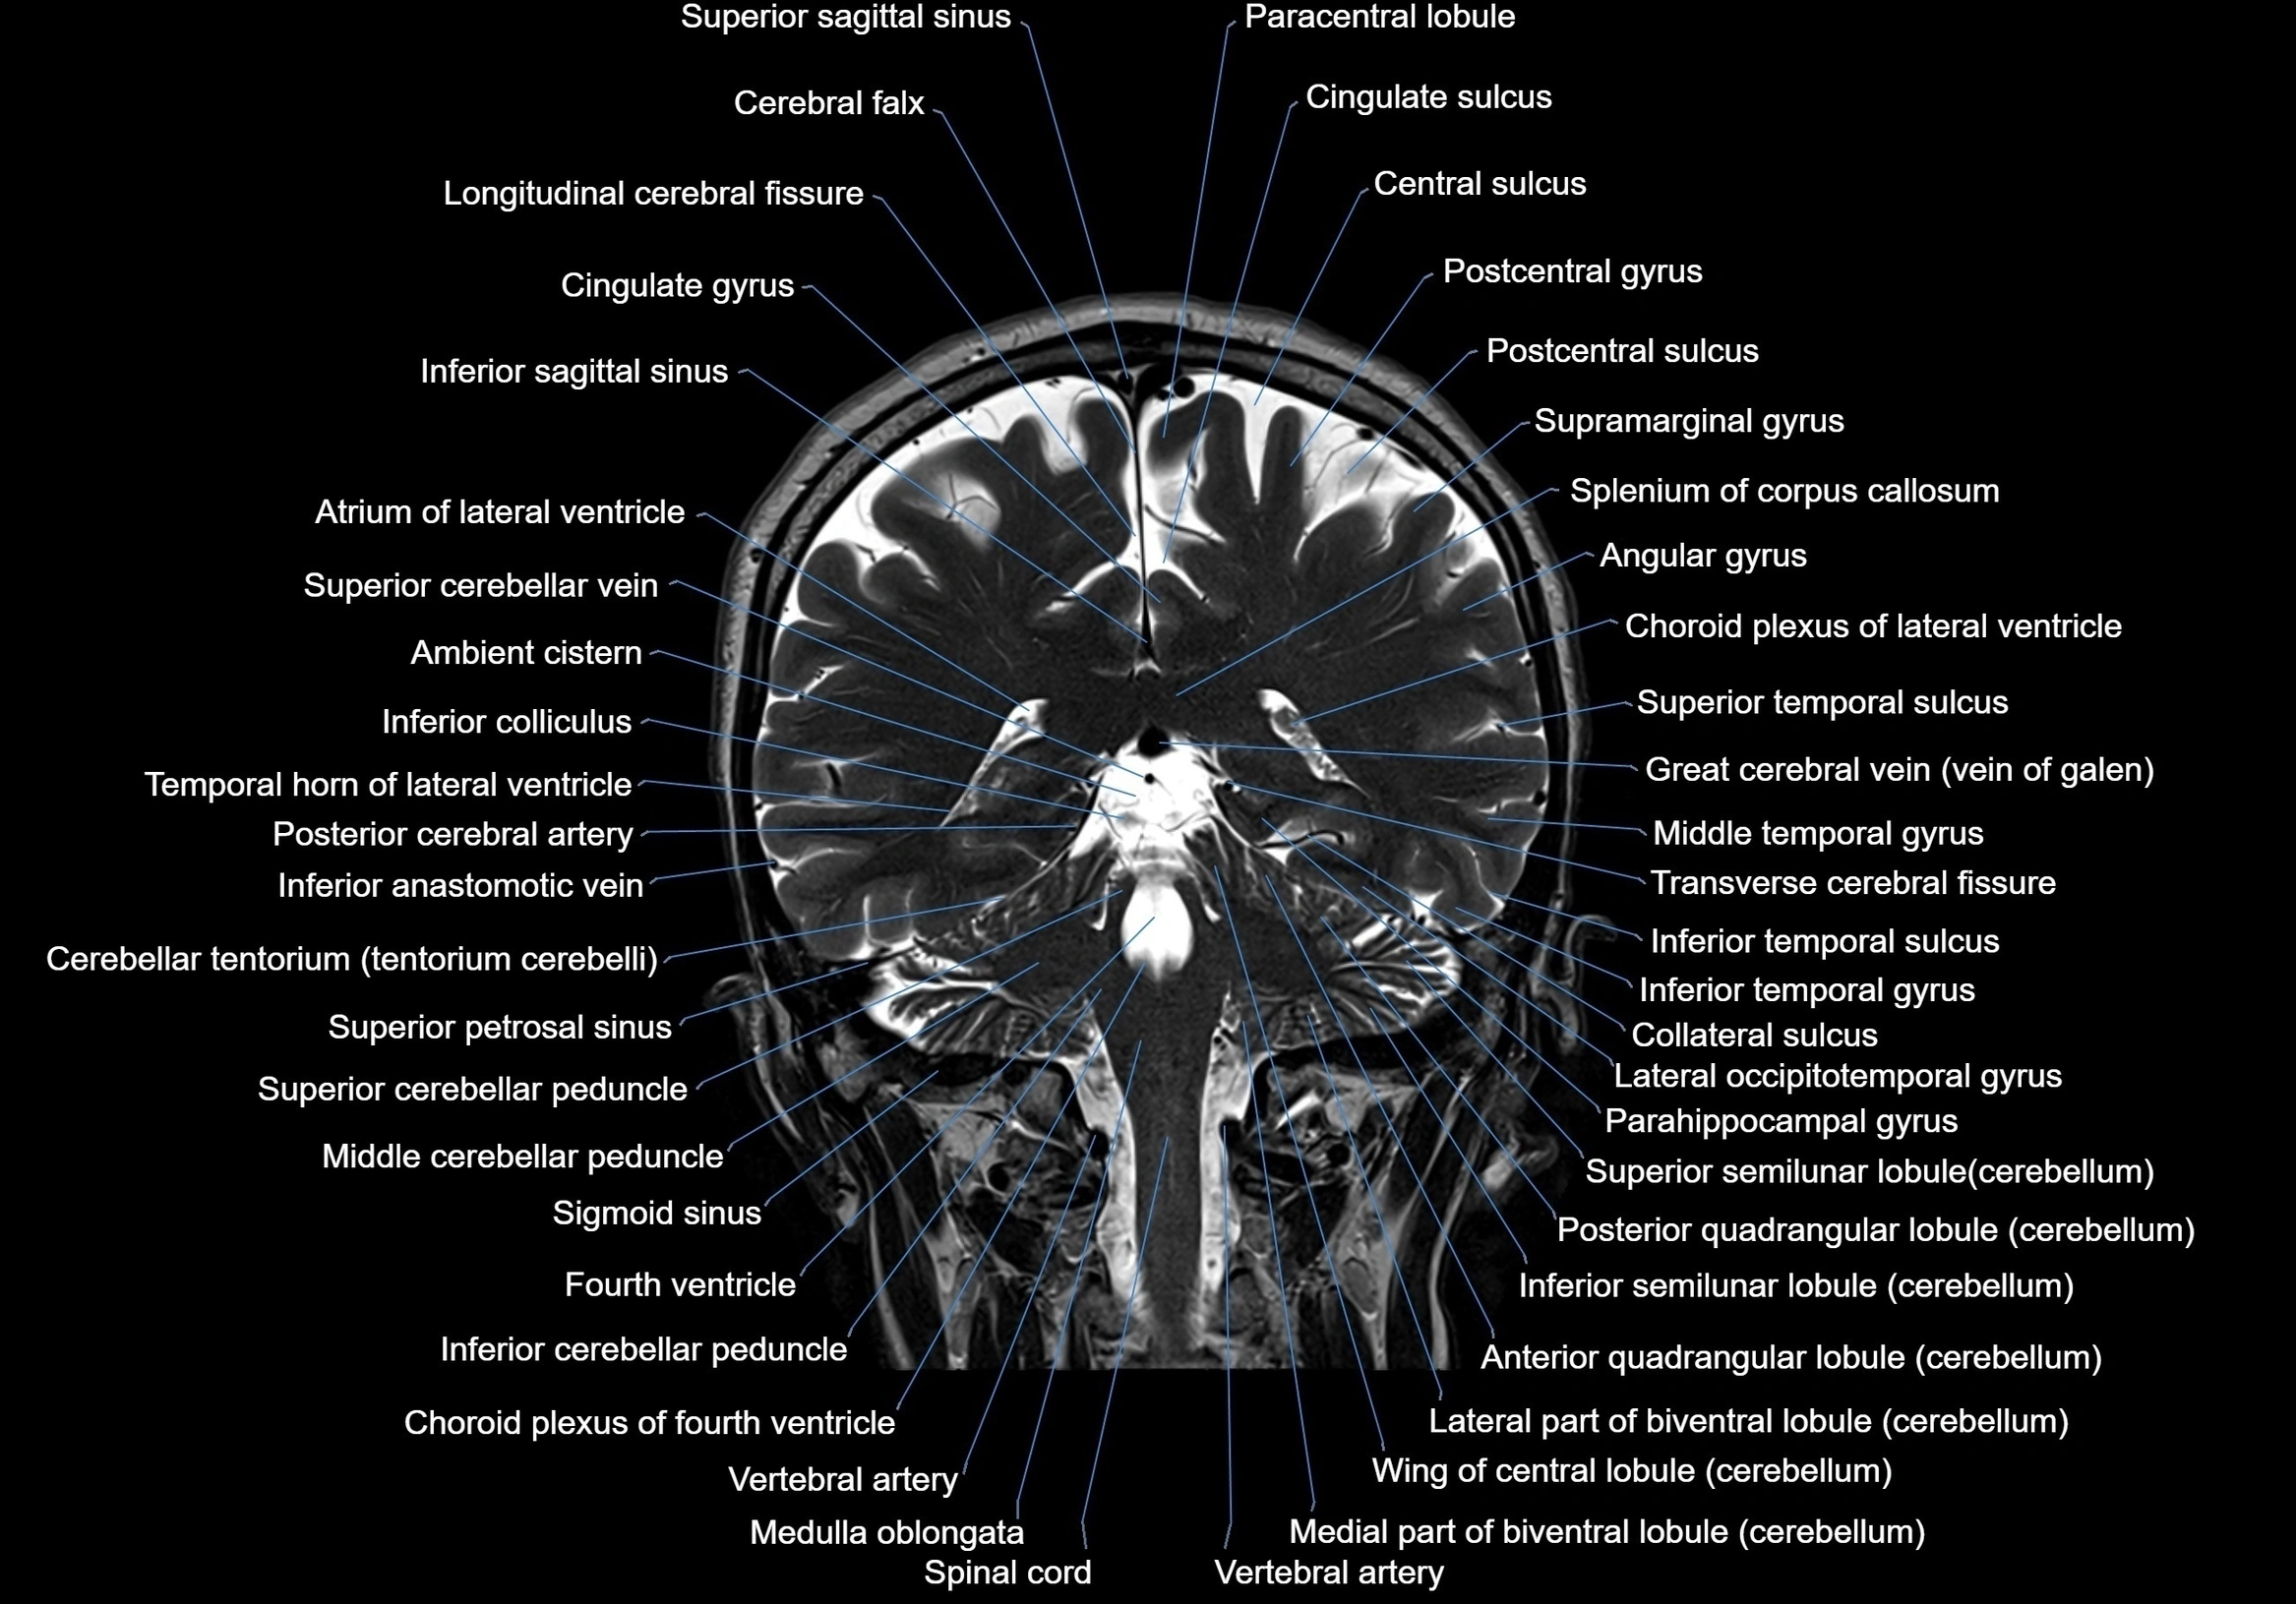

- Inferior cerebellar peduncle

- Inferior colliculus

- Inferior sagittal sinus

- Inferior salivatory nucleus

- Inferior semilunar lobule

- Inferior temporal gyrus

- Inferior temporal sulcus

- Lateral occipitotemporal gyrus

- Longitudinal cerebral fissure

- Medulla oblongata

- Middle cerebellar peduncle

- Posterior cerebral artery

- Sigmoid sinus

- Spinal cord

- Splenium of corpus callosum

- Superior cerebellar peduncle

- Superior petrosal sinus

- Superior sagittal sinus

- Superior semilunar lobule of cerebellum

- Superior temporal gyrus

- Superior temporal sulcus

- Supramarginal gyrus